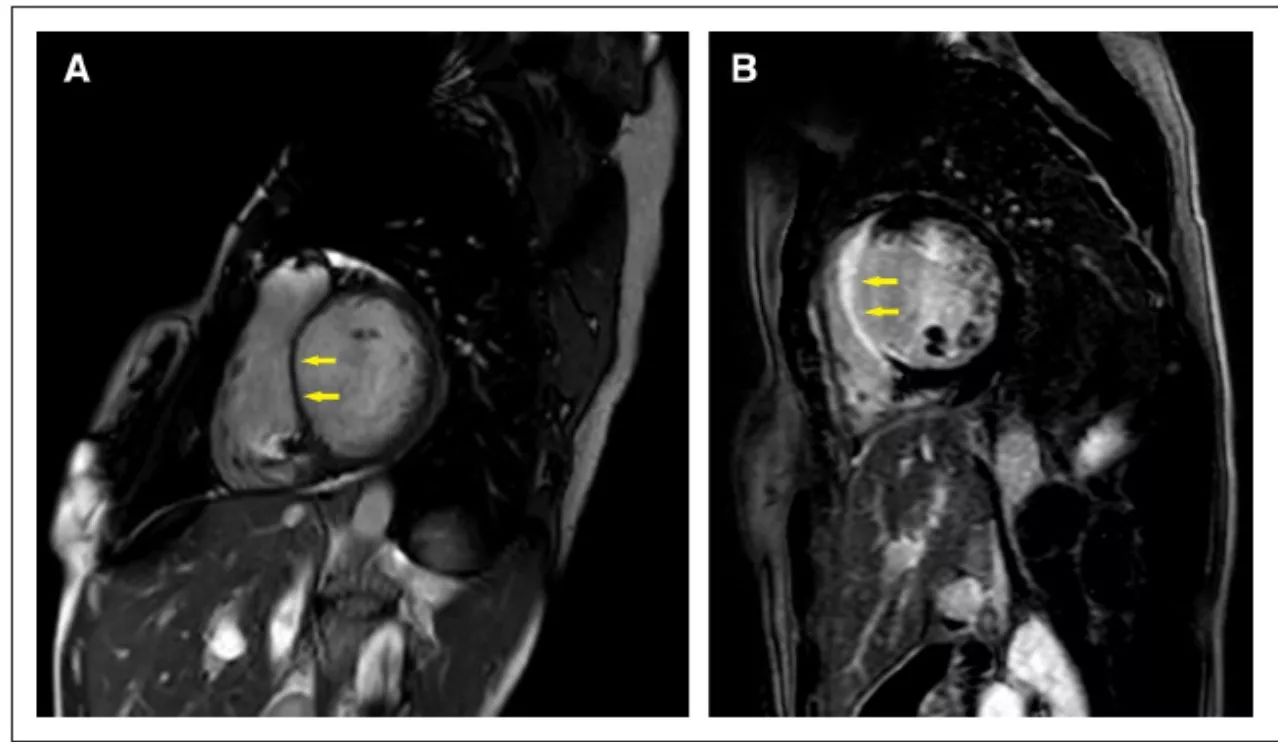

心肌结节病MRI(与ECHO同一个病例):A 左室扩大,室间隔变薄;B 局部室间隔全层钆延迟增强(LGE)

(CircRes.2017;121:819-837)